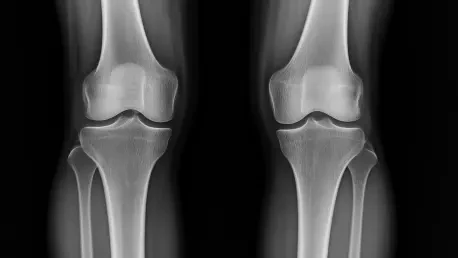

At the heart of this advancement lies a sophisticated generative diffusion model, a type of AI that crafts realistic future knee X-ray images up to a year ahead. Trained on nearly 50,000 X-rays from almost 5,000 patients—one of the largest datasets of its kind—this system doesn’t just predict; it visualizes. Alongside each image, a risk score quantifies the likelihood of disease progression, offering a dual lens of insight that blends visual and numerical data for a comprehensive outlook.

What sets this tool apart is its efficiency and clarity. It operates nine times faster than comparable models and in a more compact form, making it practical for busy clinical settings. Additionally, the AI pinpoints 16 specific areas on the knee joint in its generated images, showing exactly where changes are expected. This transparency tackles a common flaw in earlier AI systems, which often left doctors guessing about the basis for predictions, paving the way for greater trust in machine-assisted diagnostics.

Imagine a patient sitting in a doctor’s office, staring at two X-rays side by side—one showing their knee today, the other a predicted image of next year. This stark comparison can turn vague warnings into tangible urgency, prompting adherence to physical therapy or weight management plans. For many, seeing the potential wear and tear firsthand cuts through denial or procrastination, fostering a proactive mindset that could delay severe outcomes.